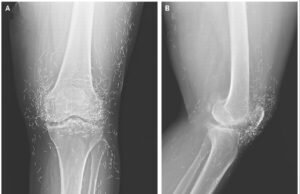

Dilema de diagnóstico: dor intensa no joelho de uma mulher revela...

Paciente: Mulher de 65 anos na Coréia do SulSintomas: O paciente teve um diagnóstico anterior de Osteoartrite O joelho - um estado degenerativo do...